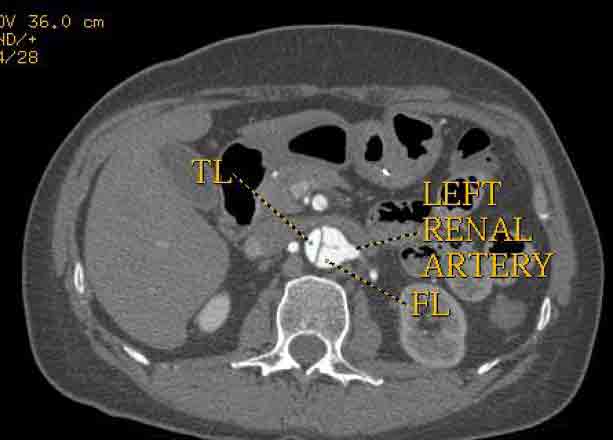

The patient was taken to the hybrid operating suite and a thoracic aortogram was performed. The aortogram confirmed the chronic Type B aortic dissection with a patent false lumen and a fenestration just beyond the left subclavian artery. An intravascular ultrasound (IVUS) was also performed of the entire aortic arch and descending thoracic and abdominal aorta. The IVUS also confirmed that there was an adequate proximal landing zone beyond the left subclavian artery consisting of normal aorta where we would be able to achieve adequate seal of the endovascular stent graft. The septal fenestration began approximately 1.5 cm distal to the left subclavian artery. The true lumen was compressed distally. (Figure 2) The celiac artery appeared to come off the true lumen. (Figure 3) The dissection extended into the superior mesenteric artery and the artery was perfused from both the true and false lumen. (Figure 4) The left renal artery came off the false lumen. (Figure 5) The right renal artery came off the true lumen.